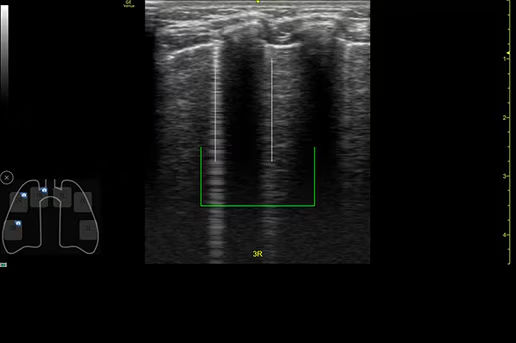

Review lung segment images in one view with Lung Diagram

A single view diagram of anatomical lung segments with one click image storing. Keeps track of segmental lung assessment and can be helpful in showing trends in response to therapy.

featurecard-lung-diagram-desktop